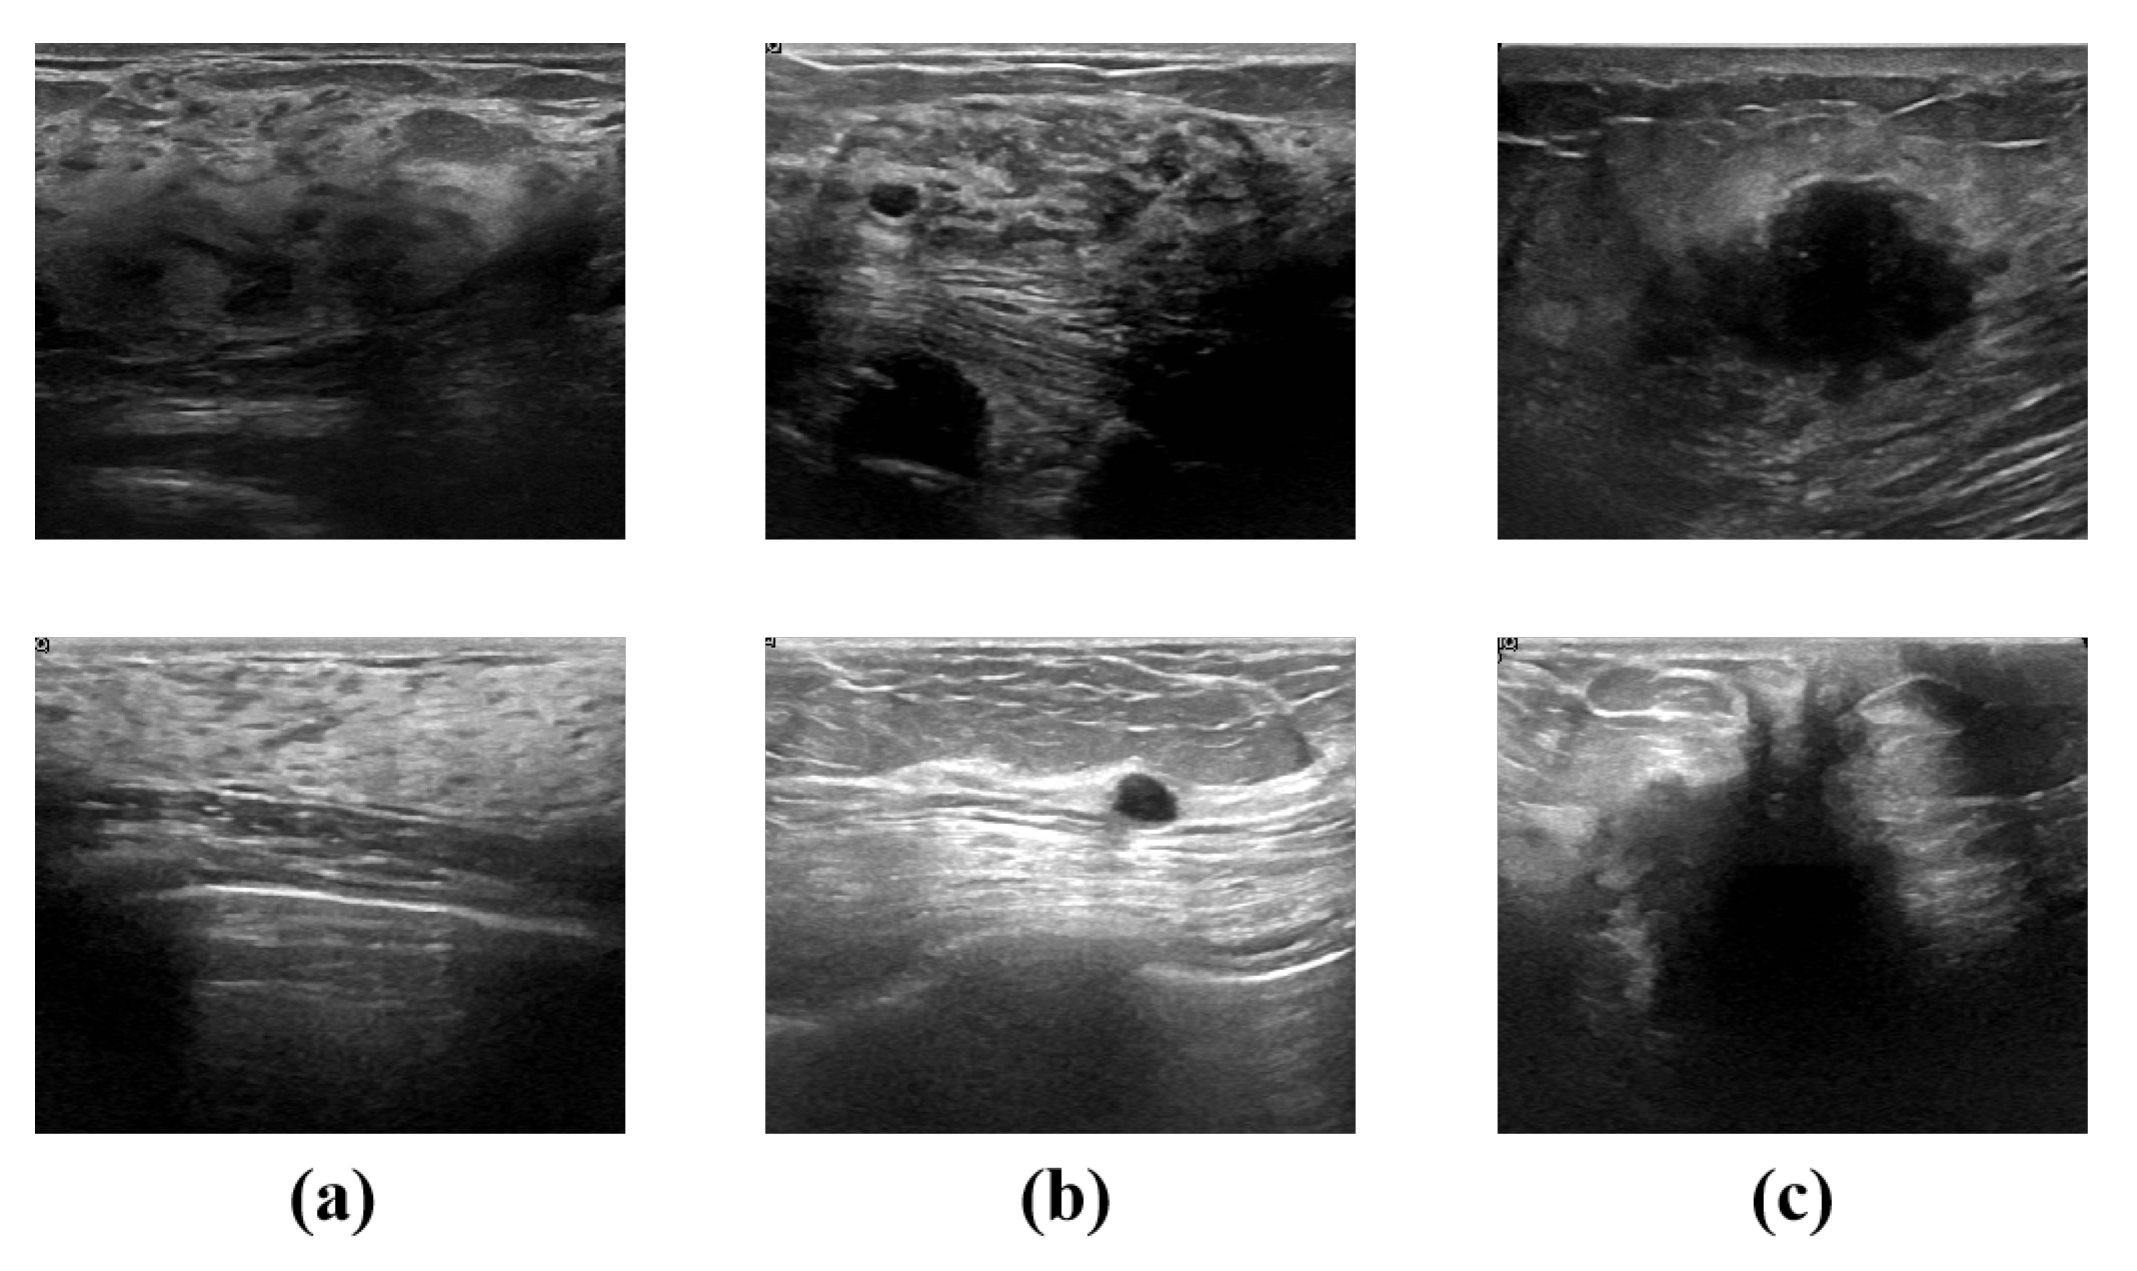

4.1. Dataset